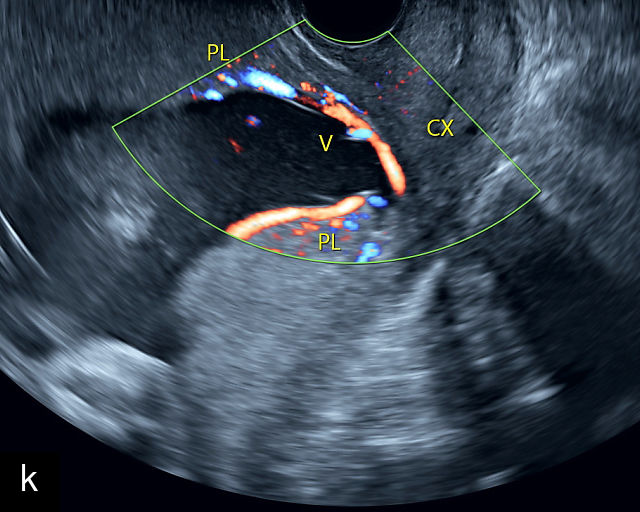

5

Placenta previa and low-lying placenta. (a) Transabdominal grayscale ultrasound image suspicious for placenta previa. The placenta (PL) appears to overlie the internal cervical os (CX). Note the time stamp: 2:19:37. (b) Transvaginal ultrasound of the same patient taken approximately 50 minutes later. Note the time stamp: 3:10:25. The internal os and the lower placental edge are both clearly seen, and the placenta does not overlie the internal os. Because the lower placental edge is 1.93 cm from the internal os, it will likely resolve by the third trimester. (c) Transabdominal grayscale ultrasound of placenta previa. The placenta (p) covers the cervix, but the cervix, especially the internal os, cannot be visualized due to shadowing. (d) Transabdominal grayscale ultrasound of placenta previa. The placenta (p) covers the cervix (c) but shadowing obscures adequate visualization. The internal os is indicated by the arrow. (e) False-positive image of placenta previa on transabdominal grayscale ultrasound. The bladder (b) is full, pushing the anterior and posterior walls of the lower uterine segment (ls) together making it appear that the placenta (p) overlies the internal os of the cervix. In reality, the line depicted by the arrowheads is where the anterior and posterior walls of the lower segment are in proximity to each other. The cervix is much lower and is obscured by shadowing (c). (f) Transabdominal grayscale ultrasound image of placenta previa. The placenta (p) covers the cervix (c), but the cervix, especially the internal os, cannot be visualized due to shadowing. b, bladder. (g) Transvaginal grayscale ultrasound image of placenta previa. The placenta (p) completely covers the internal os (arrow) of the cervix (c). The internal os can be seen clearly. h, fetal head. (h) Transvaginal grayscale ultrasound image of posterior low-lying placenta (p). The lower placental edge is clearly seen and is 1.56 cm from the internal os (arrow) of the cervix (c). The placental edge and the internal os are clearly seen. h, fetal head. (i) Transvaginal grayscale ultrasound image of a posterior placenta previa (p). The internal cervical os is clearly seen (arrow). c, cervix. (j) Transvaginal grayscale ultrasound image of an anterior placenta previa (p). The internal cervical os is clearly seen (arrow). c, cervix; h, fetal head. (k) Transvaginal grayscale ultrasound image of a posterior placenta that was thought to be low-lying on transabdominal sonography but could not be adequately assessed. This examination clearly shows the lower edge of the placenta (p) to be 2.18 cm from the internal os (arrow) of the cervix, firmly establishing that the placenta is not low-lying and allowing the patient to undergo labor safely and deliver vaginally. c, cervix. (l) Transvaginal grayscale ultrasound image of placenta previa. The placenta (p) completely covers the internal os (arrow) of the cervix (c). The internal os can be seen clearly.